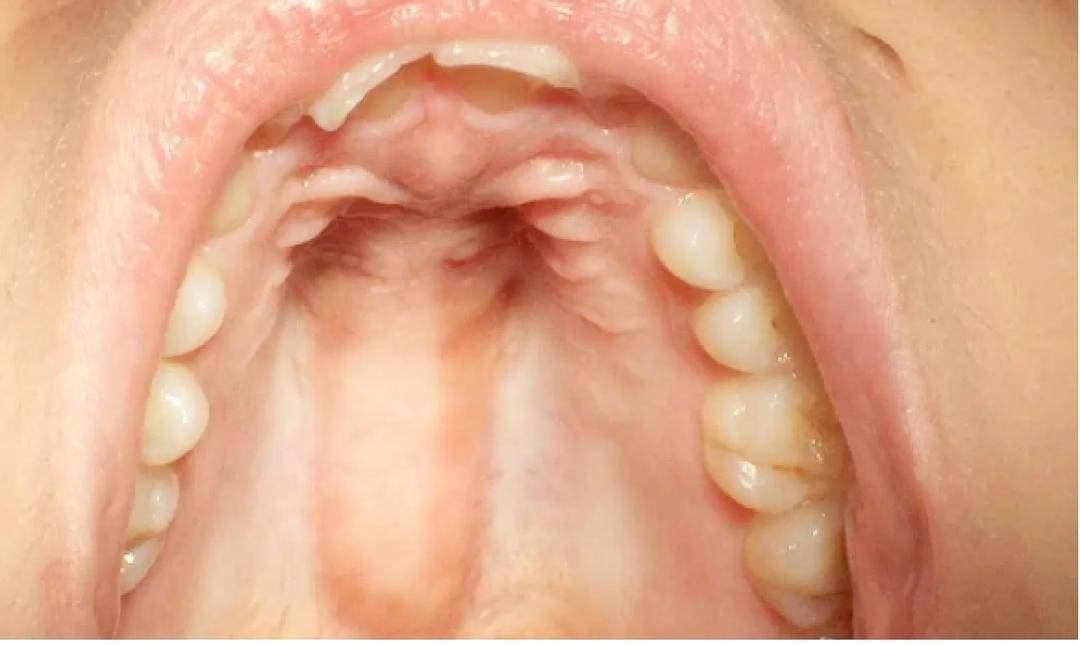

Torus Palatinus adalah pertumbuhan tulang yang terletak di atap mulut (langit-langit keras). Muncul di tengah langit-langit keras dan dapat bervariasi dalam ukuran dan bentuk.

Meski begitu, kondisi ini tidak berbahaya dan menyakitkan Ada sekitar 20 hingga 30% populasi di dunia memiliki torus palatinus. Ini paling sering terjadi pada wanita dan keturunan Asia.

- Terletak di tengah atap mulut kamu.

- Ukuran bervariasi, dari lebih kecil dari 2 milimeter menjadi lebih besar dari 6 milimeter.

- Memiliki berbagai bentuk, datar, nodular, berbentuk spindle, atau terhubung dan berkelompok.

- Pertumbuhan lambat. Biasanya dimulai pada pubertas tetapi mungkin tidak terlihat sampai usia paruh baya.

- Seiring bertambahnya usia, Torus Palatinus berhenti tumbuh dan dalam beberapa kasus, bahkan mungkin menyusut, berkat resorpsi alami tubuh tulang seiring bertambahnya usia.